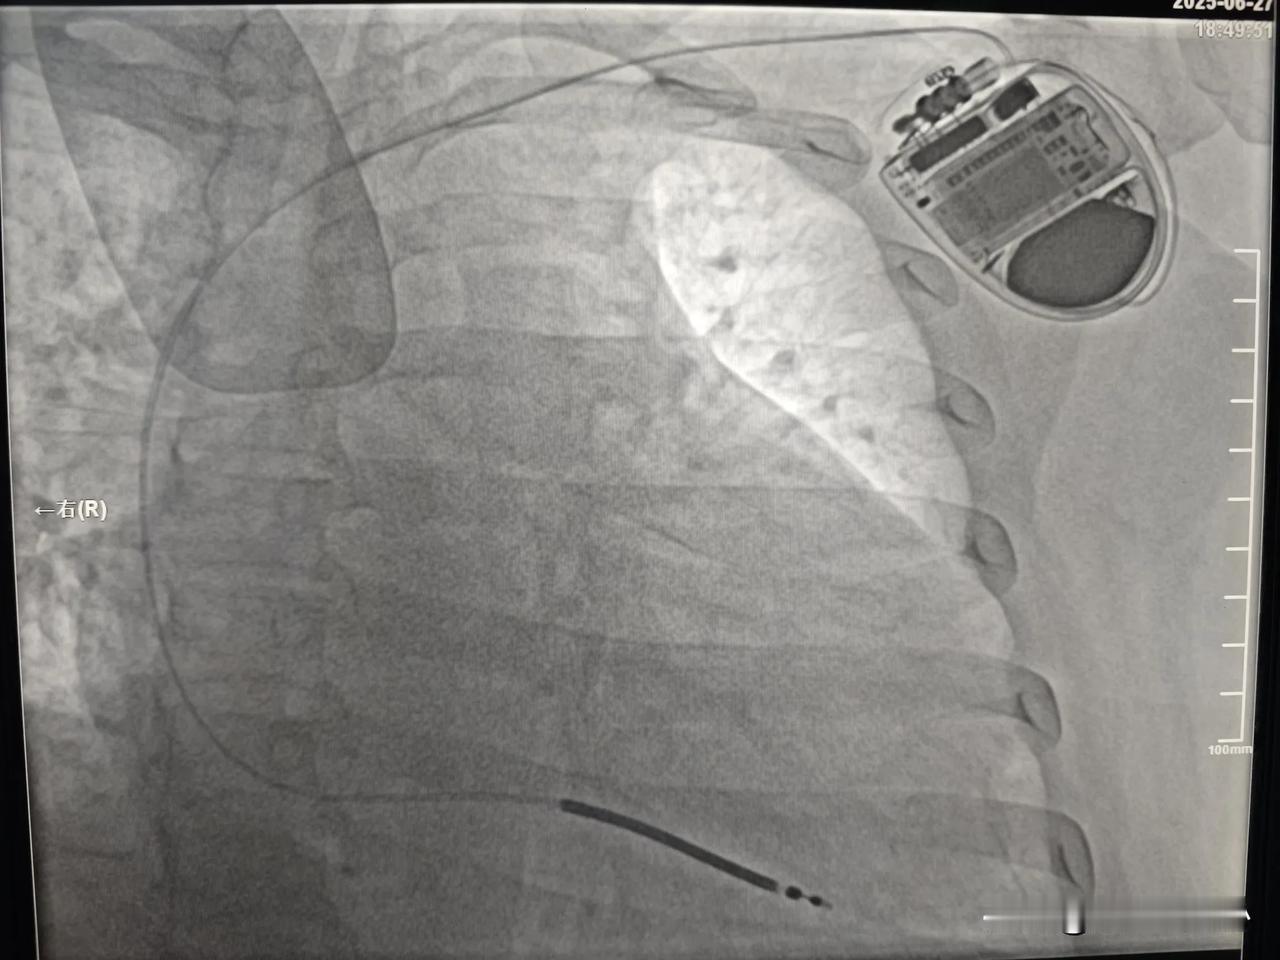

今天没有做冠心病相关手术,今天做了3台心脏起搏器手术。 第 1 台是一名65岁女性患者,体检发现心动过缓,最慢心跳每分钟29次,有高血压病史,合并有胸闷感觉,经常看科普的朋友都知道,这么慢的心率很容易引起晕厥和心脏骤停。今天在局麻下做了双腔心脏起搏器,连接心脏起搏器和导线的一刻,心跳恢复到每分钟60次。听到监护仪上规律的滴滴声,满满的安全感,再也不用担心突然晕厥了。 第 2 台是一个8年前植入心脏起搏器老年患者,因起搏器电池耗竭,更换了新的起搏器,简单说就是心脏起搏器没电了,换了一个新的起搏器。 第 3 台是一个35岁青壮年男性。这个患者病情最特殊,他很年轻只有35岁。这么年轻心衰却很严重,左心室已经扩大到7.7厘米了,正常左心室只有5厘米左右。住院后多次监测到该患者出现室性心动过速。室性心动过速是一种非常危险的心律失常,如果没有及时恢复心率,患者生命随时就会终结。在医院可以用电除颤终止这种恶性心律失常,在家里如果发作了怎么办?没有及时电除颤,患者极有可能会猝死。最好的办法就是植入ICD(植入型体内除颤仪)。这种除颤设备体积很小,只有半个手机大小,放置在左侧锁骨下方的皮肤下面,电极连接到心脏,时刻监测患者的心律情况,一旦发现室性心动过速,即可发放电脉冲终止这种危险的心律失常,成为患者存活的最后一道防线,希望他健康地活着。